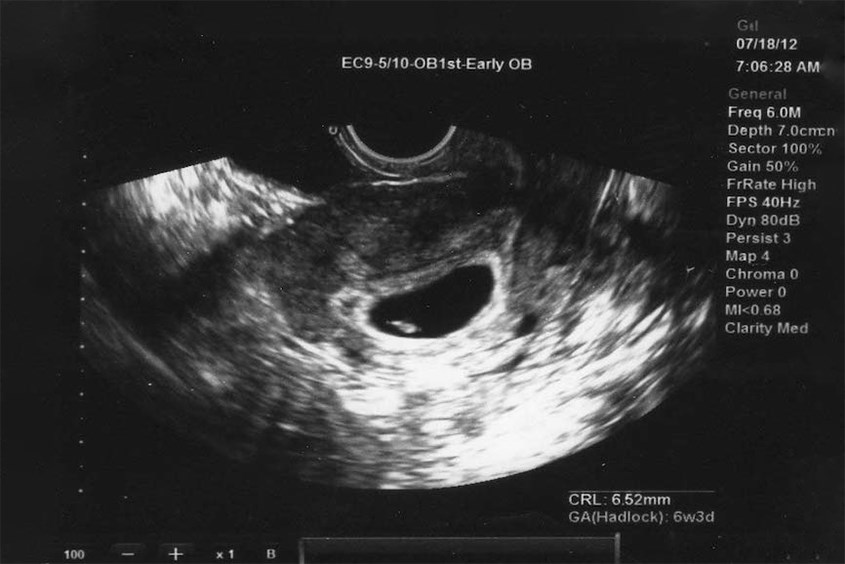

Hình ảnh siêu âm thai nhi 4 tuần tuổi

Hình ảnh thai nhi 4 tuần tuổi

5.4. Thai nhi 4 tuần tuổi có siêu âm được không?

Siêu âm khi thai nhi 4 tuần tuổi chỉ có thể xác định được kích thước và vị trí trứng làm tổ, chưa thể nghe được tim thai. Tuy nhiên, vì kích thước quá nhỏ nên siêu âm đôi khi cũng rất khó thấy.